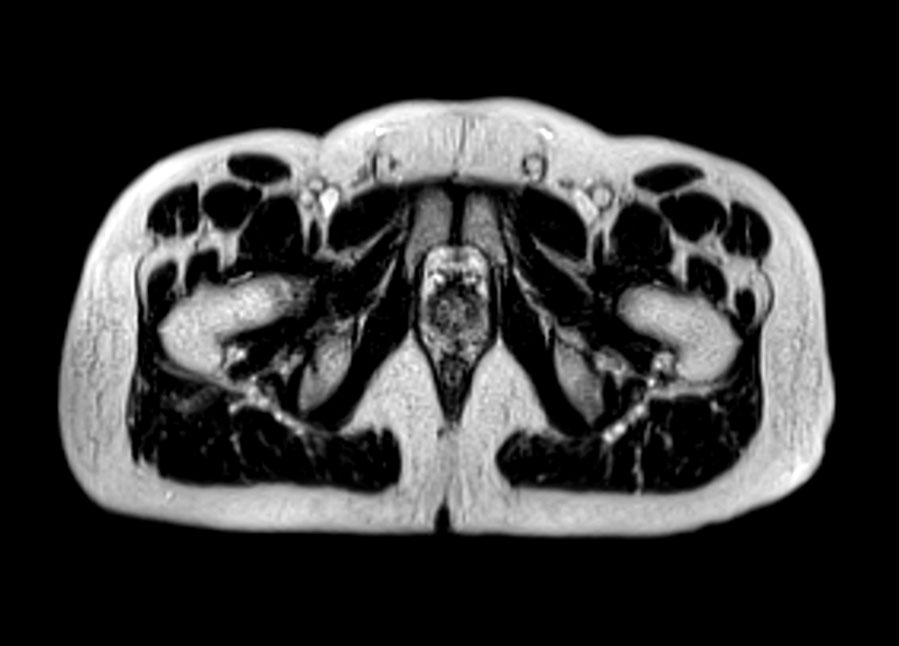

Hassas konturlama ve daha az kenar boşluğu sağlamak için CBCT’ye kıyasla üstün doku görselleştirme

SmartVISION ®

MRI GÖRÜNTÜLEMEDE TANI KALİTESİ